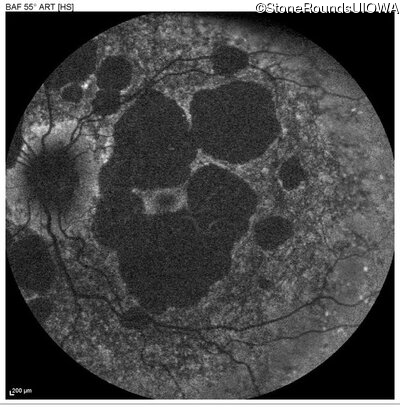

AR Stargardt Disease (IIA)

Age at visit: 51 years

This 51 year old woman first experienced some abnormality in her distance vision when she was 27 years old. She feels that her vision has been stable since that time.

Diagnosis & molecular findings

Disease Gene Allele 1 variant(s) Allele 2 variant(s) Inheritance mode

AR Stargardt Disease ABCA4 Gly1507Arg GGG>AGG IVS42+1 G>A AR